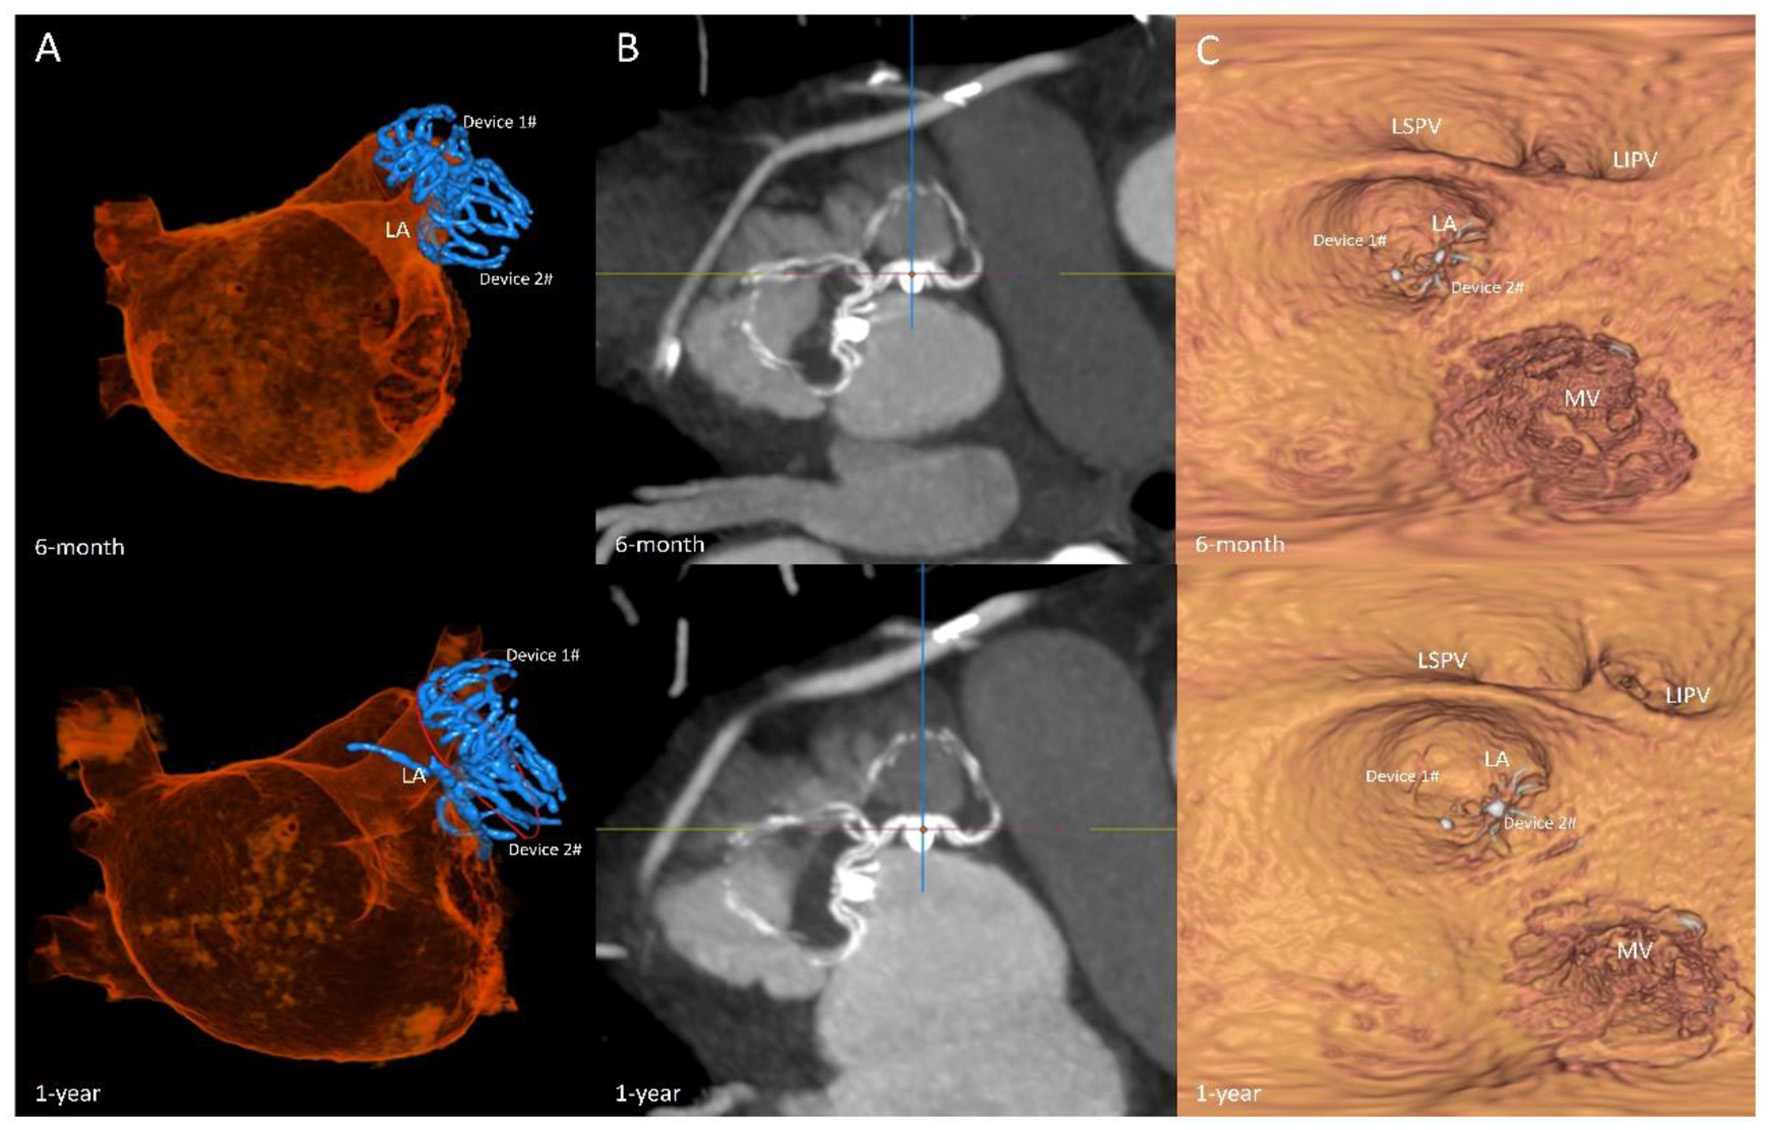

Among the 7 patients, 1 patient developed pericardial effusion during the 7-day perioperative period. The patient was discharged from the hospital after pericardiocentesis and drainage and adjustment of anticoagulants. TEE and CCTA were obtained at 7 days, 6 months, 1 year, and 2 years post-operatively to monitor device residual shunt, device-related thrombosis, and adverse events and to evaluate the effectiveness of occlusion. Follow-up results are shown in Table 2. There was no device embolization, thrombosis or obvious peridevice leakage (≥l mm) during the 2-year follow-up, with the exception of 2 patients with 2 mm of incomplete LAA sealing. The residual shunt occurred in the free links between the occluder and the rim of the defect or the occluder itself. Over time, endothelialization covered the surface of the packer and then reduced the residual shunt. The 6-month and 1-year follow-up images of one patient are shown in Figure 5.

Figure 5

Follow-up imaging. Multiplanar reconstruction evaluating the anatomic position (A); volume-rendering CT image evaluating the residual shunt after surgery (B); multiplanar reconstruction evaluating the endothelialization of the occlusions (C).

To ensure the long-term efficacy of LAAO, TEE and CCTA are commonly used to monitor device residual shunts, device-related thrombosis, and adverse events to evaluate the effectiveness of occlusion (13, 14). In our follow-up study, TEE and CCTA were obtained at 7 days, 6 months, 1 year, and 2 years post-operatively to evaluate the effect of occlusion. Four patients underwent CCTA, and two underwent TEE. In patients who underwent complete LAA closure with dual devices, residual shunts were observed in 28.6% of patients (2 of the 7 patients) in our center. Fortunately, none of our 7 patients developed device-related thrombi.